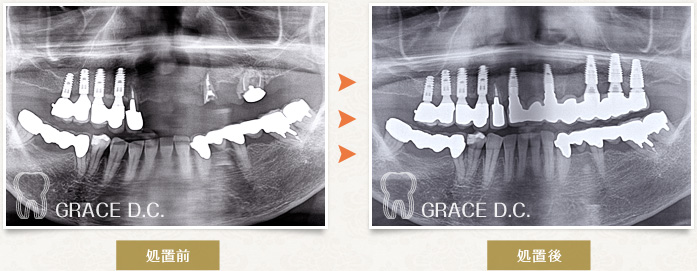

| 主訴・治療内容 | 上顎前歯部Brに入れ歯をかけてあまり噛めないながらも食事をしていた患者様。前歯のBrが噛み合わせの力によるダメージの蓄積で壊れてしまい何とかしっかり噛みたいという希望がございました。 抜歯後早期にインプラント6本埋入、暫間的に義歯を装着していただき、インテグレーションを待って仮歯にて経過を見て、その後最終上部構造を装着し、上顎をインプラントにて回復させた症例です。 |

|---|---|

| 費用 | インプラント手術26.4万円×6本、カスタムアバット4.4万円×6本、 仮歯2.2万円×6本、ダミーの歯3,300円×6本、 最終上部15.4万円×6本+ダミーの歯11万円×6本 |